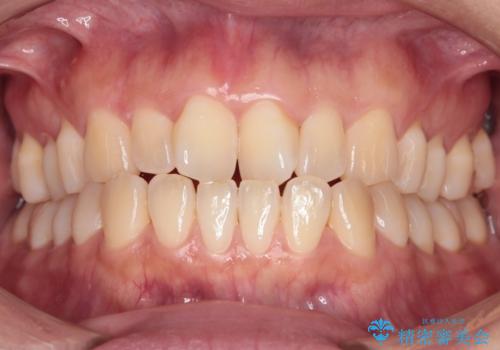

前歯の隙間とへこみが舌で触ると気になる|矯正治療は絶対にしたくない|抜歯即時インプラント+オールセラミッククラウンで審美修復

外科処置は一度だけ|抜歯即時インプラントで短期間で自然な見た目へ

前歯の変色が気になる〈セラミッククラウン〉

担当医 瀧村怜未